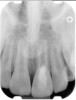

Fig 1. Preoperative radiograph showing apical bone loss.

Figure 1

Clinical procedure: If apical bone loss is present (Figure 1) a collagen/gelatin sponge (eg, Gelfoam®, Pfizer Inc., www.pfizer.com) can be placed apically so that the MTA can be delivered to the desired working length. (Any other surgical resorbable sponge would also work, such as OraPlug® [Salvin Dental Specialties, www.salvin.com], Surgifoam® [Midwest Dental, www.mwdental.com], or Surgispon® [Aegis Lifesciences, www.surgispon.com]). This is done by taking a small piece (2 mm x 2 mm) of the resorbable sponge and pushing it down to and through the root apex with an endodontic file. Once this is done, MTA is packed down the canal with a custom-fitted cone. The clinician can use a rubber stopper on the gutta-percha cone to know the exact length of MTA placed in the apical third (Figure 2). Once the apical third is sealed with 3 mm to 5 mm of MTA, the remaining coronal canal space can be back-filled using a warm gutta-percha technique (Figure 3).